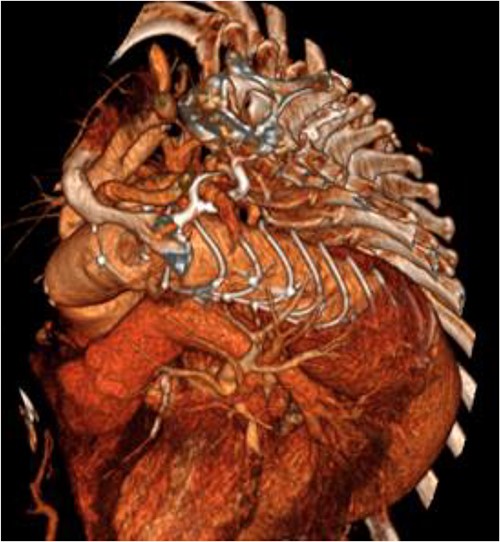

An 8 mm Gelweave graft was anastomosed to the left subclavian artery. Standard cannulation technique was used with the distal aorta and the right atrium. The distal aorta was sized and a 30/32 mm (15 cm length) Thoraflex graft was anastomosed with 4–0 prolene and reinforced with 1.5 cm Teflon. The supra-aortic vessels were reimplanted separately; deep hypothermia (20°C) was utilized for neuroprotection with antegrade cerebral perfusion and near infrared spectroscopy monitoring. Proximal aorta anastomosis followed patient rewarming. Her post-op CT aorta showed adequate perfusion and FET placement. A 3D reconstruction is shown in Figs 2 and 3. She was discharged on Day 10 and successful TEVAR was undertaken 8 months later (Fig. 4). Follow-up 24 months later showed no evidence of endoleak, stent migration or fracture.

3D reconstructed CT thoracic aorta image showing successful FET implantation and TEVAR.